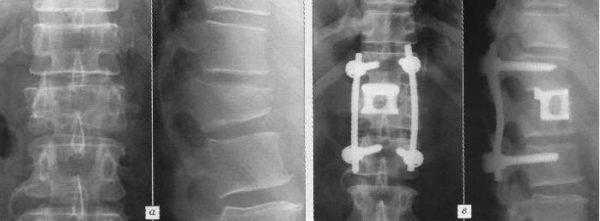

МРТ до операции

Пример лечения перкутанной транспедикулярной фиксацией спондилодисцита

После длительного курса лечения антибиотиками выполнена транспедикулярная фиксация системой viper II